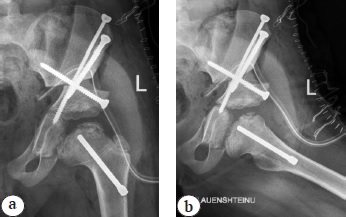

A triple pelvic osteotomy was chosen as a surgical treatment technique, which was supplemented by implantation of an orthopedic electret "Electret stimulator of osteoreparation — IMPLESO" (Medel LLC, Russia) into the neck and head of the femur in such a way that its proximal part was transfisually brought as close as possible to the focus of necrosis in the femoral head (Fig. 1).

Fig. 1. Postoperative X-ray images of the patient, born in 2015: a — AP projection; b — axial projection. The proximal part of the orthopedic electret is brought through the neck of the femur physis to the focus of head necrosis as close as possible